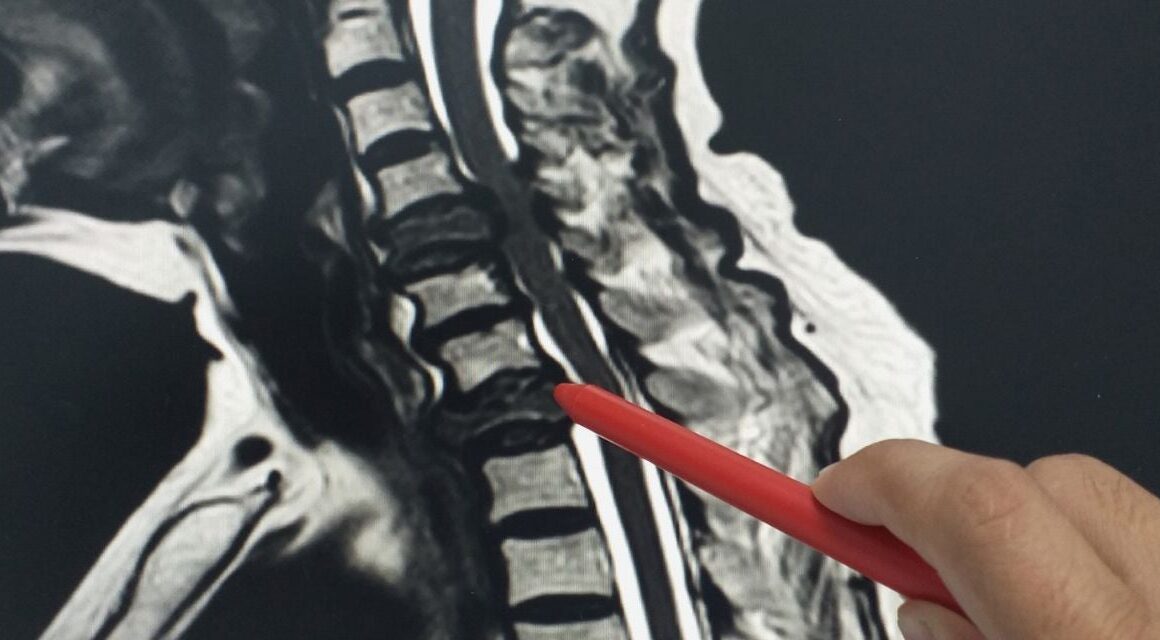

Аналитическая группа под руководством доктора Александры Шнайдер, главы рабочей группы по экологическим рискам Центра Гельмгольца, тщательно изучила влияние тропических ночей на вероятность инсульта. В ходе исследования они обнаружили увеличение частоты инсультов в тропические ночи на семь процентов.

В исследовании использовалась информация за 15 лет о 11 000 инсультов из неврологического отделения университетской больницы Аугсбурга. Доктор Ченг Хэ, главный автор этого исследования, отмечает, что пожилые люди и девочки наиболее восприимчивы. После жаркого вечера в клиниках обычно диагностируют инсульт по деликатным признакам.